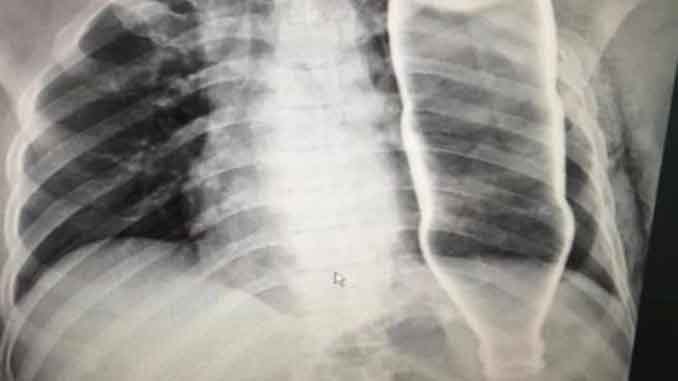

Sau khi tiếp nhận bệnh nhân, BV đã tiến hành chụp X-quang và CT, các bác sĩ ngỡ ngàng khi thấy một vỏ chai thủy tinh còn nguyên vẹn trong lồng ngực bệnh nhân B.

Sau tai nạn, ông B. bị gãy hai xương sườn nhưng không có tổn thương nghiêm trọng nào khác. Sau khi hội chẩn, các bác sĩ đã tiến hành mổ cấp cứu để lấy vỏ chai ra khỏi lồng ngực ông B.